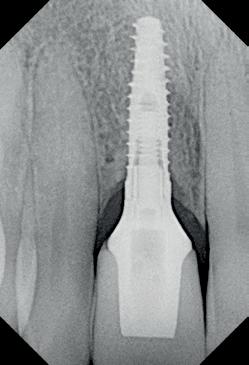

4. Pre-chirurgische OPG.

Na het klinische onderzoek volgde het röntgenologisch traject. De CBCT liet precies zien wat we al vreesden: een front waarin het bot onregelmatig was, duidelijke radiolucenties rond de pijlers en een infectiegebied dat zich onder vrijwel de gehele brug had verspreid. Tegelijkertijd was er ook potentie. Net voldoende botstructuur om immediate implantaatplaatsing te overwegen, mits alles perfect gepland zou worden.